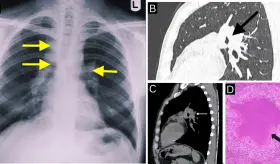

Más de 180 tipos de saborizantes en productos de vapeo pueden generar sustancias tóxicas al ser calentados, lo que aumenta el riesgo de daño pulmonar.